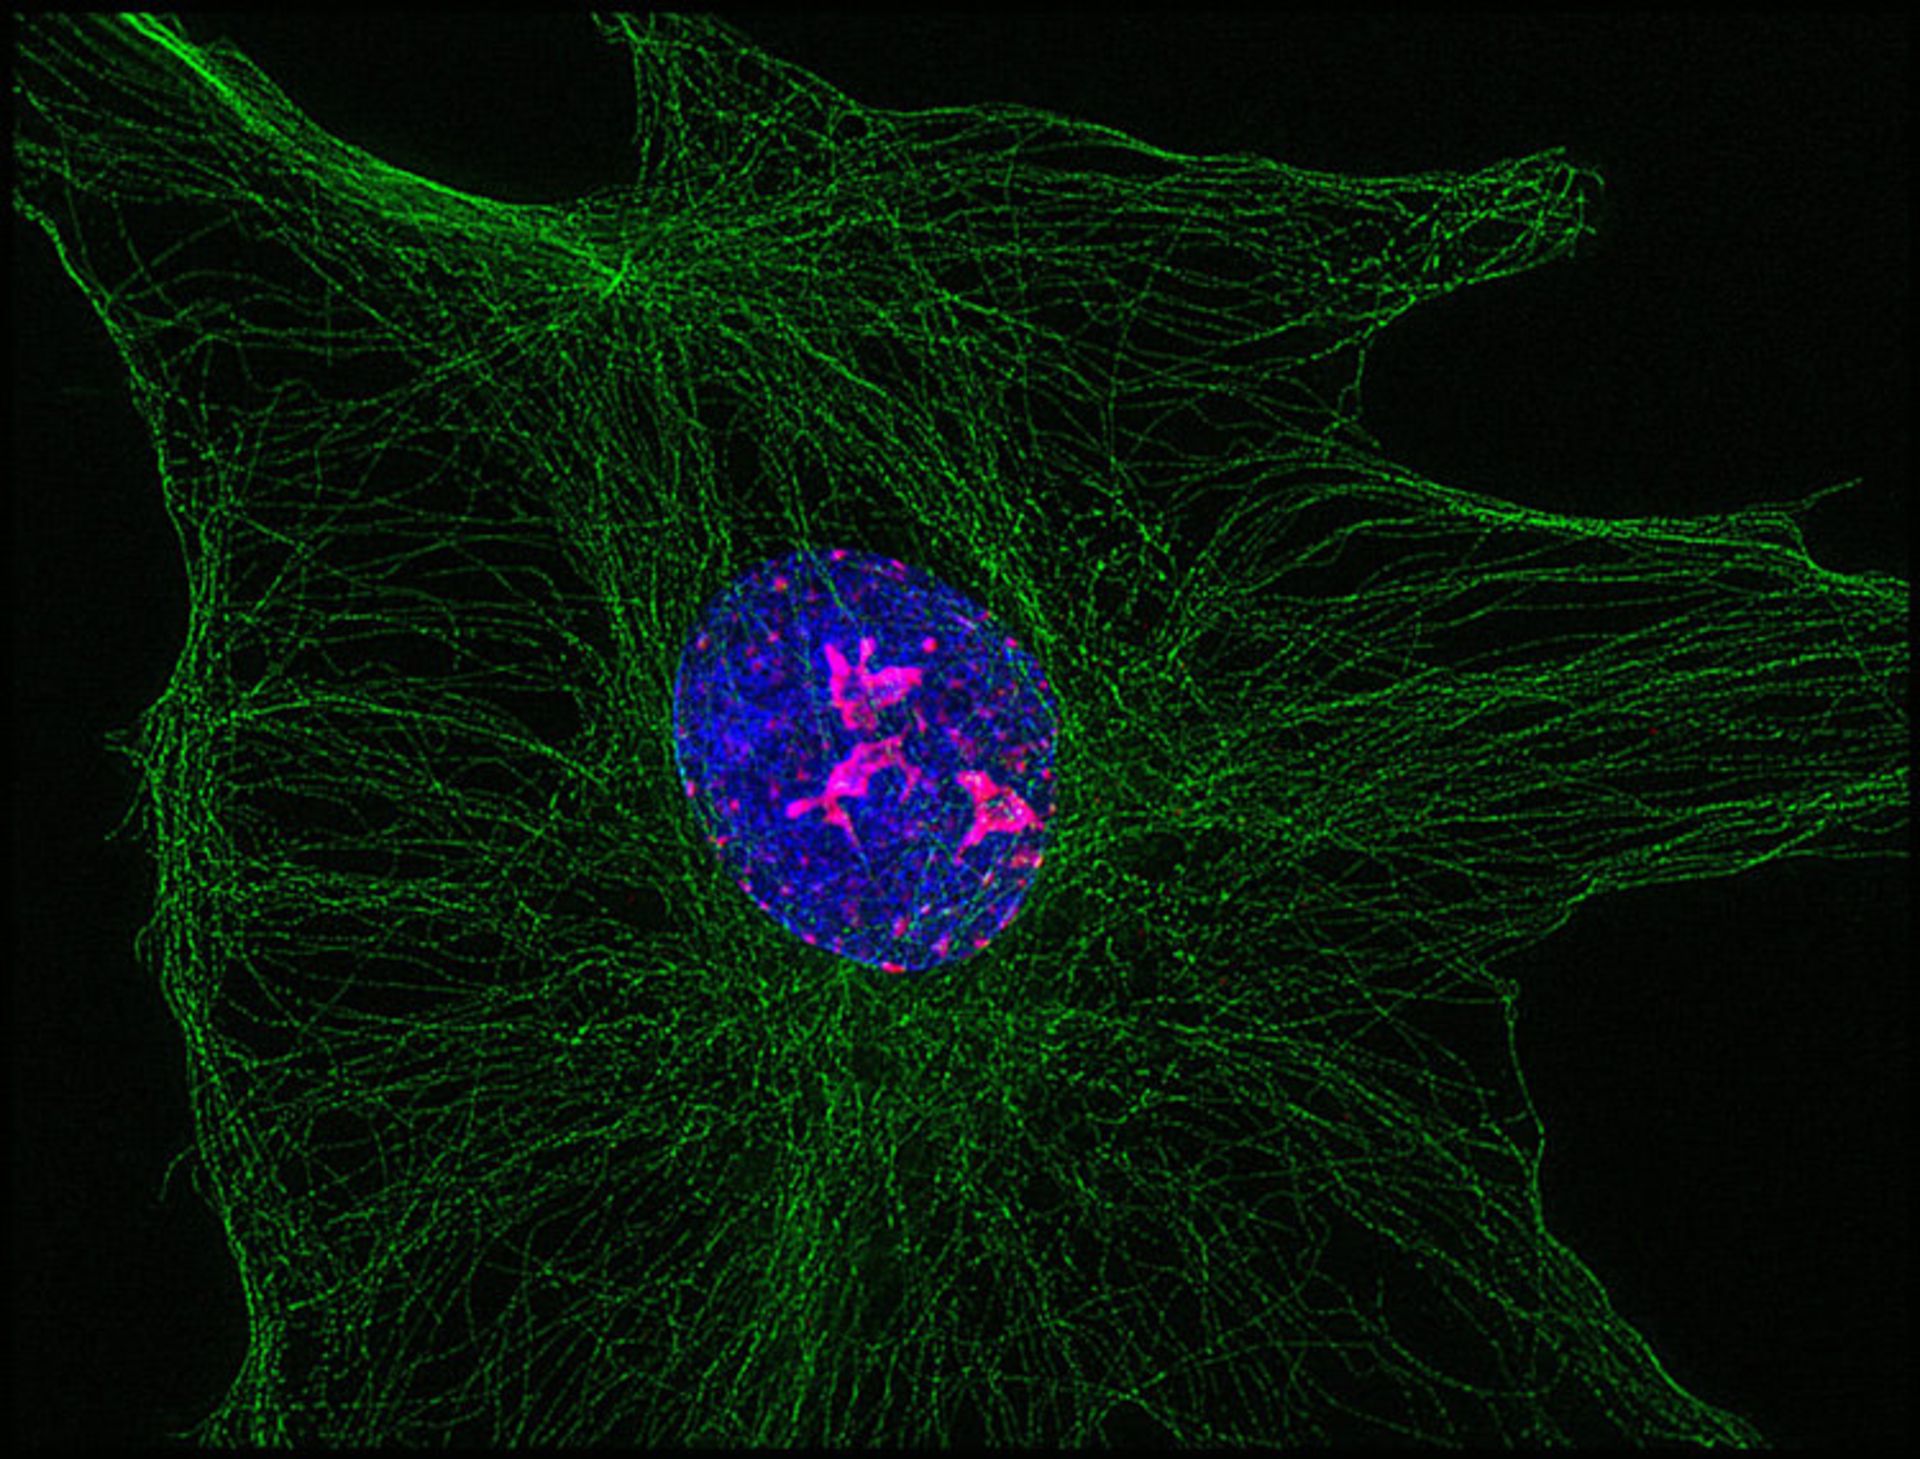

تکثیر ویروس هرپس ۸ انسانی (HIV-8)، عامل بیماری سارکوم کاپوسی (بهرنگ ارغوانی) در هستهی رگهای خونی (بهرنگ آبی)، ساختار پروتئینی سلول (توبولین) به رنگ سبز نمایش داده شدهاست ؛ بزرگنمایی ۱۰۰ برابری

آنتونی برنت ایسون (Anthony Brent Eason) از آمریکا